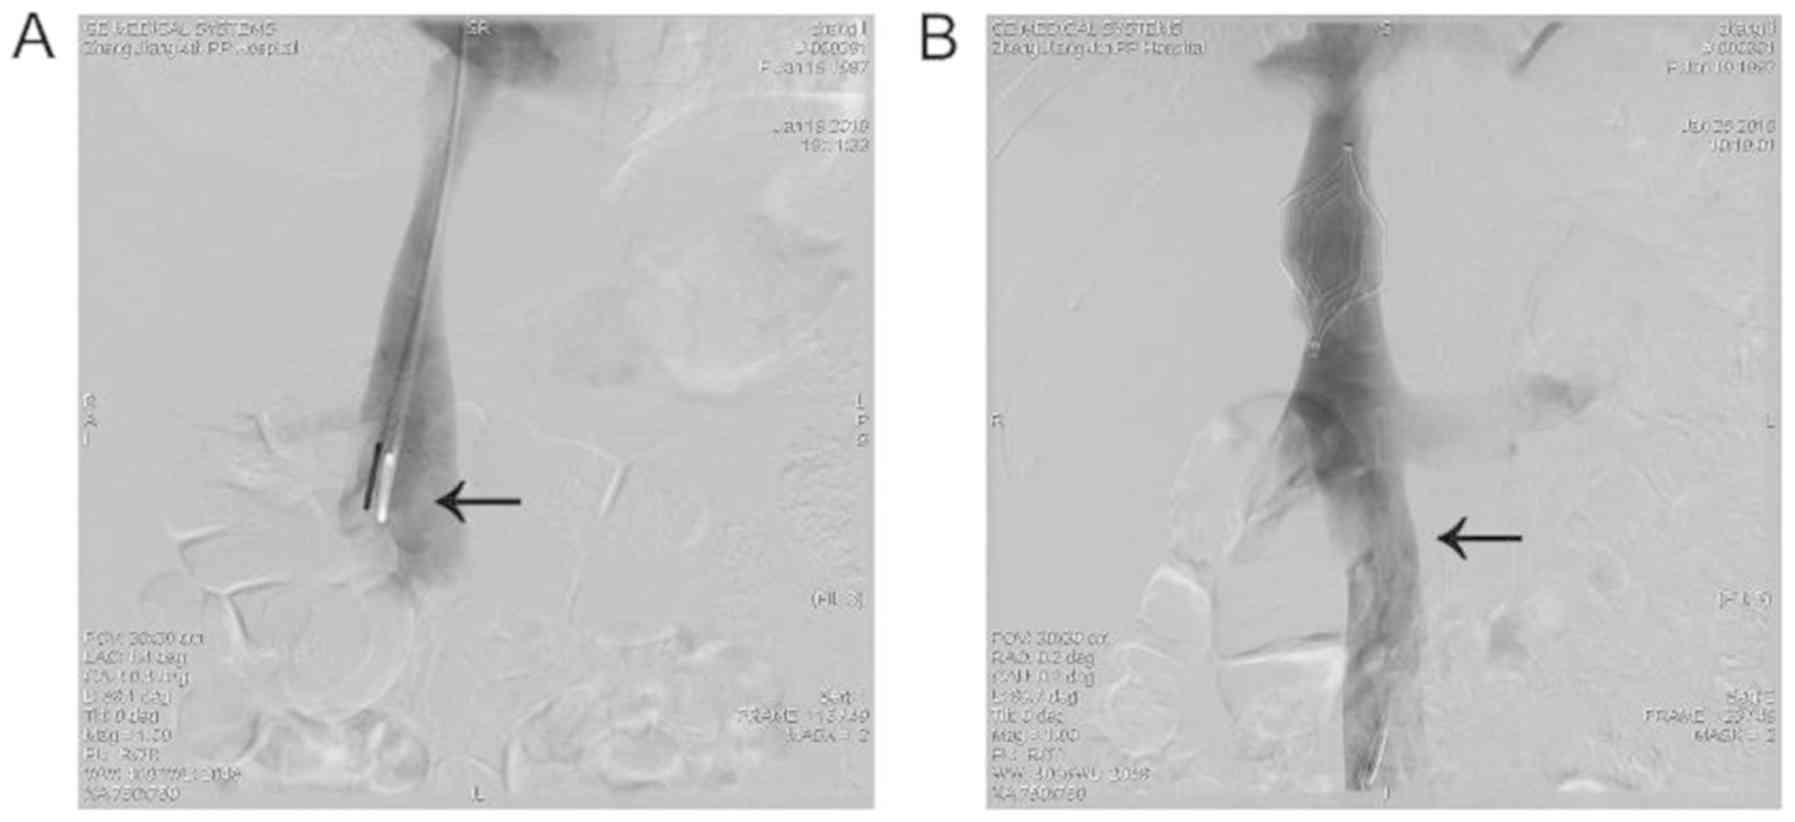

The treatment of ovarian and inferior vena cava thrombosis is determined using the clinical scenario and patient symptoms (10). An anticoagulant therapy was started with a subcutaneous injection of low molecular weight heparin calcium (0.4 ml, every 12 h for 7 days), urokinase as a thrombolytic agent intravenous drip (25 UI/ day for 3 days). Inferior vena cava filters can be implanted for postpartum OVT to prevent PE. A vena cava filter (Cordis) was implanted via the right internal jugular, which was followed by recanalization of the occluded IVC with the help of a guide wire and catheter (Fig. 2A). A trans-catheter intravenous thrombolysis was subsequently conducted. On day 10 following inferior vena cava filter implantation, the filter was retrieved through the right internal jugular after thrombus was sufficiently dissolved. This was confirmed via angiography, where the thrombus in the inferior vena cava disappeared and recanalization of blood flow occured (Fig. 2B). The patient was discharged 20 days after the completion of the procedure with no complications.

Figure 2

Inferior vena cava filters. (A) A blood clot was identified in the filter (arrow). (B) Angiography confirmed that the thrombus in the inferior vena cava disappeared, and identified the recanalization of the blood flow (arrow).